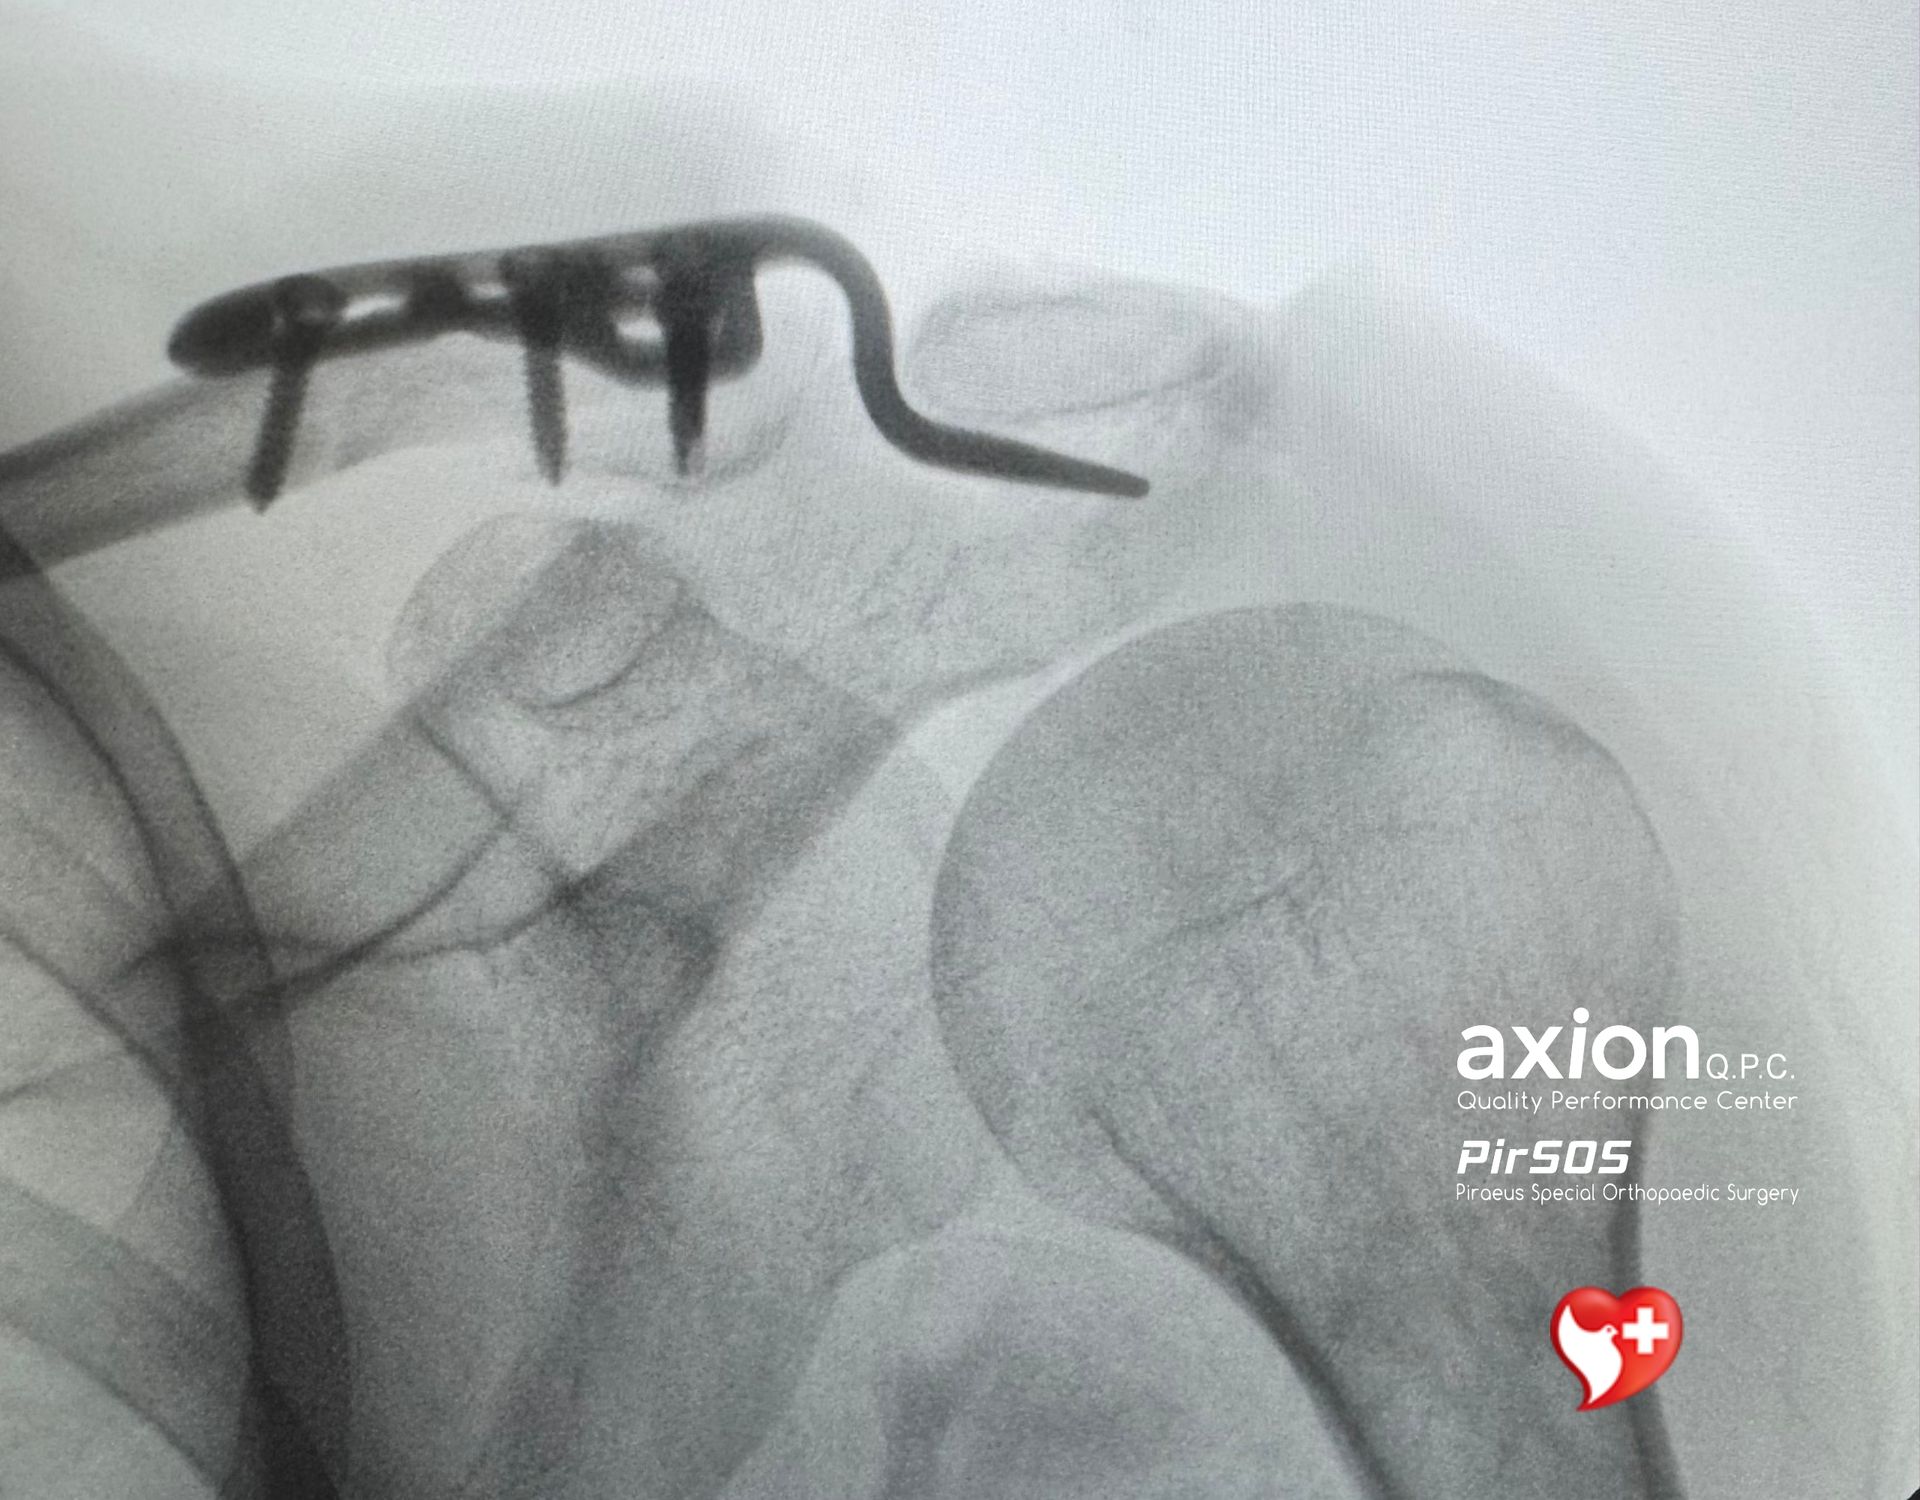

Όμως το κύριο πρόβλημα είναι ότι η hook plate δουλεύει υποακρωμιακά, άρα η ίδια η μηχανική της σχετίζεται με επιπλοκές όπως: subacromial impingement , erosion/osteolysis του ακρωμίου, άλγος, δυσκαμψία, περιορισμό ώμου, και όχι σπάνια την ανάγκη δεύτερου χειρουργείου για αφαίρεση του υλικού.

However, due to its subacromial position, hook plates are inherently associated with complications such as subacromial impingement , acromial erosion/osteolysis , pain, stiffness, limitation of shoulder motion, and not infrequently the need for a second procedure for implant removal.